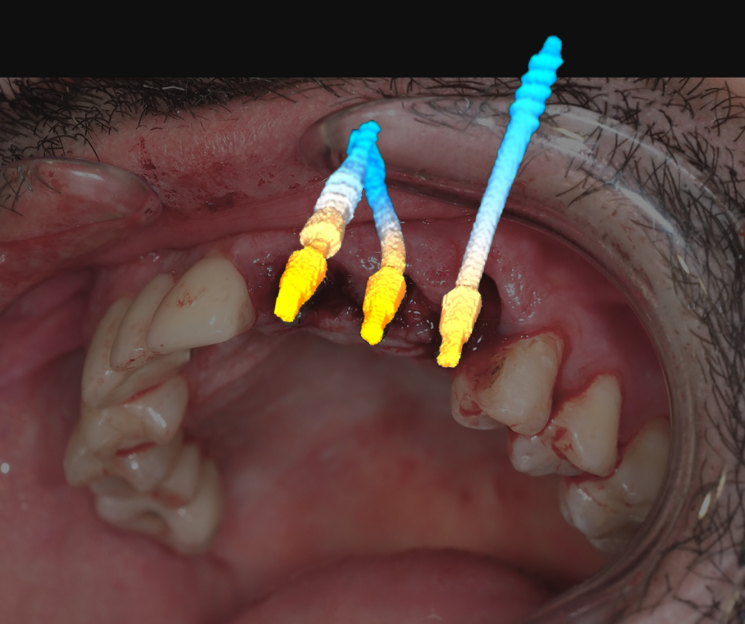

Extracción de piezas 21, 22 y 23 con infección activa

Paciente con infecciones de origen dental que comprometían severamente el hueso alveolar en la zona anterior superior. Se realizó la extracción de los dientes 21, 22 y 23, y se optó por una rehabilitación inmediata mediante implantes córticobasales.

Estrategia protésica e implantes utilizados:

- 1 implante córticobasal compresivo

- 2 implantes córticobasales rectos y finos

Esta combinación permitió anclar los implantes en hueso cortical, que mantiene su estabilidad incluso en presencia de procesos infecciosos en el hueso alveolar. El resultado: rehabilitación funcional y estética el mismo día de la cirugía.